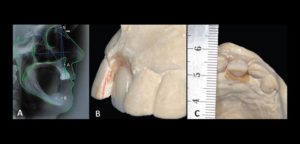

041 – Planificación y Tratamiento en Rehabilitación Oral con Prótesis sobre Implantes usando Análisis Cefalométrico

En los pacientes desdentados, que requieren una prótesis completa ya sea convencional o implanto soportada, los dientes artificiales se colocan en la prótesis completa por